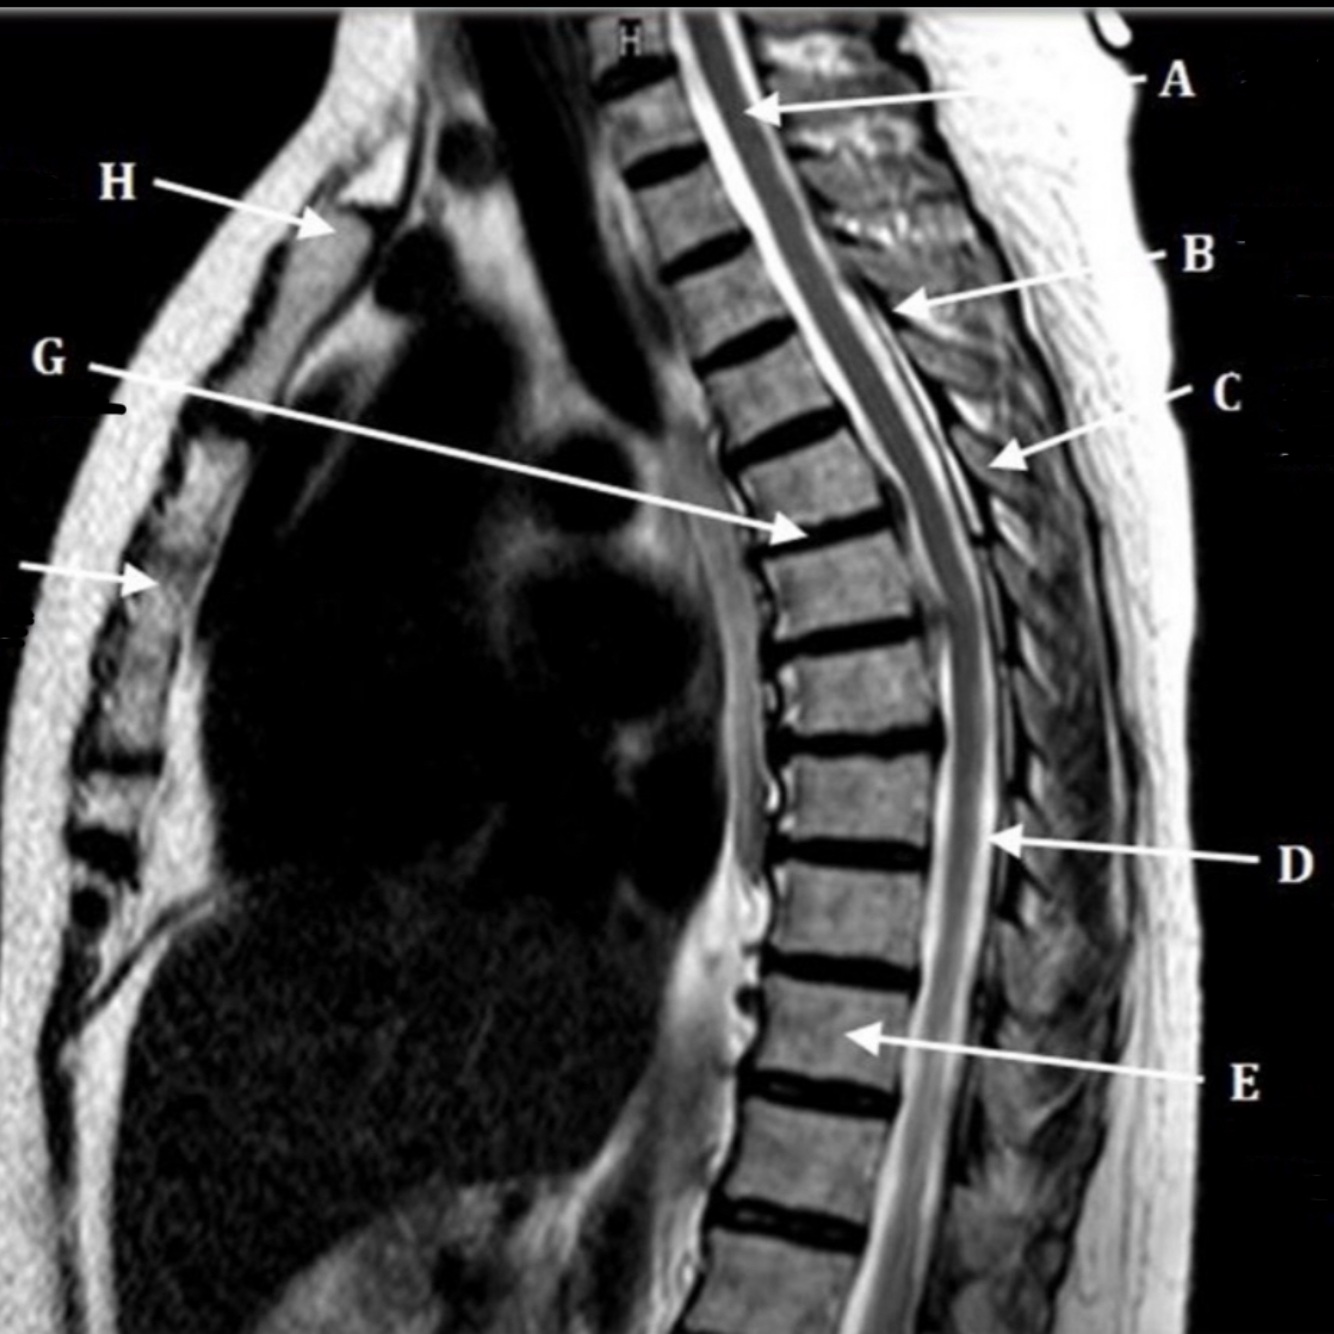

19

What is letter A?

A

SPINAL CORD

20

What is letter B?

LIGAMENTUM FLAVUM

21

What is letter C?

SPINOUS PROCESS

22

What is letter D?

CSF

23

What is letter E?

VERTEBRAL BODY

24

What is letter F?

STERNUM

25

What is letter H?

SUPRASTERNAL NOTCH